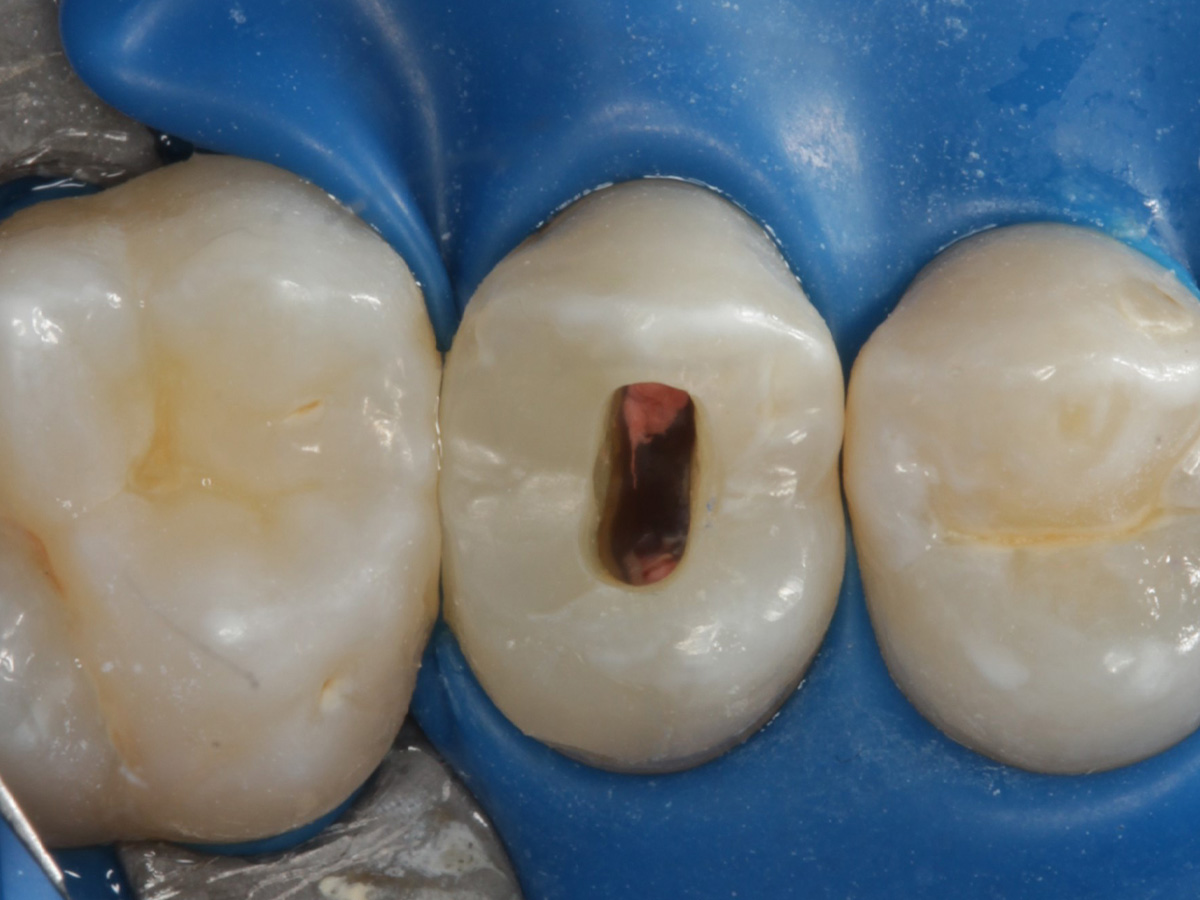

Abbildung 6

Pulpenkavum mit Watte und farbigem Komposit abgedeckt; zuvor Spülung der Wurzelkanäle nur mit NaCl zwecks Nichtgefährdung der Kompositadhäsion